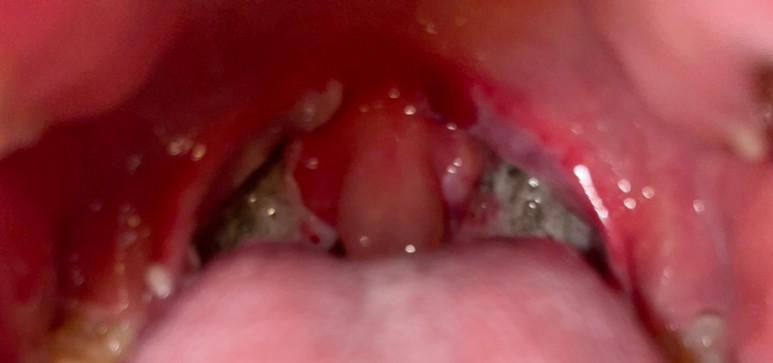

수술을 받기 전에 내 편도 아무리 양치질을 하고 이래저래 해도 없어지지 않는 면봉으로 떼어내면 피가 고여 잘 안 된다.

수술 끝나고 병실에 왔는데 너무 추웠어. 벌벌 떨면서 잠이 들었다.눈을 뜨고 나서 원장님이 오셔서 수술은 잘 되었다고 생각하는 결석뿐만 아니라 안쪽에도 결석도 많고 편도가 많이 커졌고 염증도 심해서 좋지 않았던 상태라는 것.. 흑우.. 눈을 뜨자마자 미친듯이 목이 아픈 누군가가 내 목젓을 손으로 감싸 꽉 쥐고 있는 느낌.. 침을 삼킬 때마다 한번씩 짜내는 느낌.. 너무 아파.. 수술한 뒤 오후 4시 30분 이후부터 물을 조금씩 먹으라고 한 물을 마셨는데..아파서 한 번 먹고 안마 저녁도 죽 나왔는데 못 먹겠다…

대학병원 진료는 이제 힘들다고 알고 있는데… 아무도 나를 안보는 CPR에 와서 진료가 30분정도 늦어진다… 선생님이 와서 진료할때 혈액검사 및 지혈제 주사를 맞으라고 해서 맞는데 속이 울렁거리면서 저 덩어리가 나온다… 너무 충격적이었다… 저 덩어리가 나오고 나서 내 목에 걸리는 피는 다 토해냈다 간호사 선생님이 휴지랑 컵 그리고 폐기물통을 가져다 달라고 했는데 열심히 토했다…. 그런데 토할 때마다 내 몸이 이상해 진다… 호흡기 치료를 하면서 검사 및 수액을 받고 있을 때 의비후과 담당 일단 큰 출혈이 없다고 하니 나도 동의하듯 호흡기 치료하면서 계속 목으로 뭔가 넘어가는 느낌이 들었다..순간 어지러워 간호사 선생님을 불렀는데 혈압이 조금 내려갔다며 누워 있으라고 했는데 누우면 숨을 못쉬었다…누웠다 반복하니 더 어지럽다…가능하면 나도 간호사라서 간호사 선생님은 잘 모르는데 너무 힘들고 어지러워 토할 것 같아 간호사 선생님을 찾아간다….찾아갔더니 선생님이 비닐봉지에 토해내라고 검은색 비닐봉투를 주셨다.다시 자기 자리로 돌아와 자리에 앉자마자 피를 토하는 핏덩어리와 그냥 피가 넘쳐 응급실 바닥에 흘리면서 그냥 기절… 간호사 선생님과 의사 선생님이 오셔서 정신차리시라고 했던 기억만 있다.눈을 떠보니 여느 응급실이 아닌 중증응급실에 갇힌 상태였다.간호사 선생님이 상태가 너무 안 좋아서 보호자에게 연락해야 한다고 해서 구토하고 나서 좀 나아진 것 같아요. 라고 했는데 피의 양이 너무 많아서 보호자가 필요하다고 함 간호사 선생님이 직접 아버지와 팀장에게 전화해서 방문해야 함을 설명한다.내가 간호사라서 그런지 의학용어나 인수인계를 아는 내 자신이 싫으면 동실 하면서 응급OP 내용을 묻는…(편도면 딱 봐도 나인데…) 어쨌든 팀장과 실습생이 온다. 팀장은 자리를 비우면 안 되는 상태에서 실습생이 내 간병을 해주는데 상태가 좋아져서 다시 A구역으로 옮겨지는 순간 또 울컥했고 결국 또 피를 토한다..(종이컵 2컵정도) 다시 좋아져서 실습생 보조하에 휠체어를 타고 화장실에 다녀왔다.. 화장실에서 토하고 움직이는 휠체어라도 토하고..(다행히 마스크를 쓰고 있다가 마스크가 가득 토하기도 하고) 순간 내 몸 안에 있는 장기가 터져서 이렇게 피가 나는 줄 알았다.또 자리에 앉아 눕기를 반복하지만 그럴 때마다 계속 피를 토한다… 윗배도 아팠다… 차나리 빨리 수술받고 싶었다… 아니면 이대로 죽을까 하는 생각까지 든다.또 이비인후과 담당의사가 와서 아무래도 피를 많이 토하고 있어서 응급수술을 해야겠다고 합니다.(혈압도 떨어지고 맥박수도 올라가고..) 피도 비닐봉지 하나 채울 정도로 흘리고 피의 수치도 줄여주고… 상태가 좋지 않다고 한다..) 코로나 검사결과가 나와서 수술실에 들어갈 수 있다고 한다.. 미친듯이 아프고 윗배도 답답해서 계속 토하는 내가 힘들어서 빨리 수술시켜달라고 한다.. 3시반쯤 코로나 검사결과가 나오고 수혈동의서도 서명한다.(피를 많이 토하고…) 아버지도착해서 수술동의하고 환자복을 갈아입는데… 미친듯이 피를 토한다.움직일 때마다 토하니까 미칠 것 같아.수술실로 이동하여 전신마취를 다시 하고 수술…. 전신마취를 하는 동안 산소호흡기 마스크를 올리고 이름의 수술부위를 확인하고 상처가 있는지 물어봤는데 순간 무릎 상처가 있었는데 잊어버리고 말을 못했다…. 10명 정도가 나에게 붙었는데 무서웠다…

수술이 끝나고 회복실에 있었는데.. 그때도 속이 울렁거리면서 구토한 회복실 간호사가 허겁지겁 누군가에게 연락했고, 나는 다시 기분이 좋아지는 주사를 맞았다는 것.주사를 맞고 병실로 이동하다.미친 듯이 아팠어… 목을 누군가가 바늘로 찌르는 느낌.제 수술 담당 의사와 교수님이 따로 방문하셔서 목을 보면서 수술 부위 안쪽에 출혈이 생겼다고 하셨다.제가 생각하기에는 수술이 잘못된 것보다는 기침을 하면서 자극이 생겼기 때문이라고 생각한 교수님께서도 말씀하시기에는 10000분의 1확률에 걸린 것 같다고 하셨고… (결국 운이 나빴다고 하시는데…) 제 길) 2박3일 입원해 있으면 된다고 하시는데 또 출혈이 생길 수 있다고 해서 금요일까지 입원하기로 했다.저는 일주일도 안돼서 전신마취 두번하고 수술도 두번 했다는 점에서..